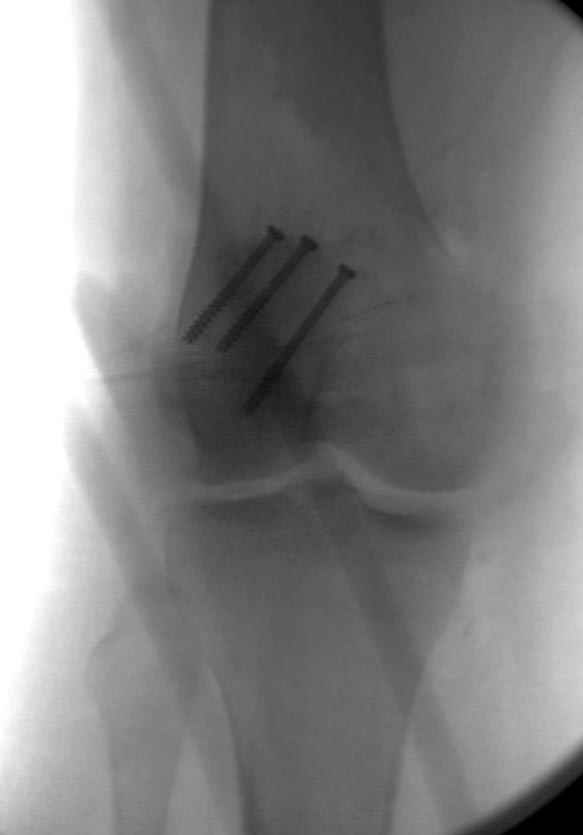

На операции: Irrigation&Debridment около 10 литров раствора, по два стержня в сегменте, фиксация диагонального, с дефектом, перелома надколенника тремя cannulated 4мм шурупами, ушивание поперечного разрыва связки 5.0 Ethibon sutures, разрыв находился на 2 см ниже надколенника (срез чем-то острым), повторная ирригация раны, взятие посева на аэробическую и анэробическую культуру, окончательная фиксация стержней наружного фиксатора 50см Carbon Fiber Bars, вакуумное закрытие. Мониторинг показал, что компартмент синдрома нет.

Сегодня досылаю остальные снимки, которые не прошли вчера. Как вчера писал, после фиксации перелома надколенника с дефектом кости и собственной связки, наложили ваккуум и наружный фиксатор. (снимки 4-9)

Внешний фиксатор держим около 6 недель, поэтому был выбран метод фиксации шурупами и еще линия перелома была диагональной, не было нужды в tension band technique, cannulated screws удобнее, провел спицы и по ним шурупы.

Связка ушита обычными сухожильными швами конец в конец, не было нужды проведения шва через надколенник, из-за ех-фиксатора.